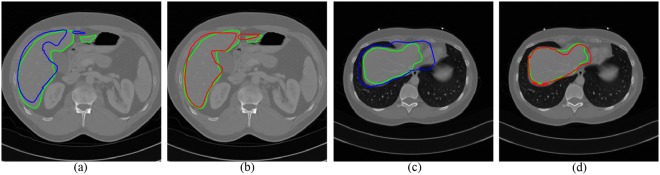

Figure 5 shows two slices of automatic segmentations by two transformation models. The green curves are the ground truth. The blue curves (see Fig. 5a,c) are the segmentation results using the affine model, while the segmentation results using the FFD model are depicted with red curves (see Fig. 5b,d). It can be seen that the deformed contours through the FFD model are closer to the liver boundary. As the shape initialization of whole framework, a combined segmentation was made by atlas selection and label fusion step.

Figure 5.

Two examples of segmentation results by different transformation models. The ground truth is shown in green curves. (a) and (c) Segmentation using the affine model (blue curves). (b) and (d) Segmentation using the FFD model (red curves).